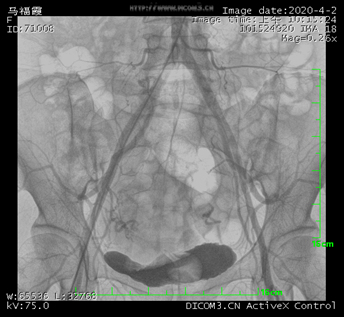

髂總動(dòng)脈造影

數(shù)字減影血管造影機(jī)((Digital subtraction angiography,DSA),一般由X線發(fā)生裝置、數(shù)字成像系統(tǒng)、機(jī)械系統(tǒng)、計(jì)算機(jī)控制系統(tǒng)、圖像處理系統(tǒng)以及輔助系統(tǒng)等組成。DSA是通過電子計(jì)算機(jī)進(jìn)行輔助成像的血管造影方法。它是應(yīng)用計(jì)算機(jī)程序進(jìn)行兩次成像完成的,在注入造影劑之前,首先進(jìn)行第一次成像,并用計(jì)算機(jī)將圖像轉(zhuǎn)換成數(shù)字信號(hào)儲(chǔ)存起來,注入造影劑后再次成像并轉(zhuǎn)換成數(shù)字信號(hào),兩次數(shù)字相減,消除相同的信號(hào),得到一個(gè)只有造影劑的血管圖像,這種圖像較以往所用的常規(guī)血管造影劑所顯示的圖像更清晰、更直觀,一些精細(xì)的血管結(jié)構(gòu)亦能顯示出來。

簡(jiǎn)單來說就是將造影劑注入需要檢查的血管中,使血管顯露原形。然后通過系統(tǒng)處理,使血管顯示更加清晰,便于醫(yī)生診斷或進(jìn)行手術(shù),這也是為什么DSA被稱為“血管機(jī)”的原因。DSA的臨床使用范圍廣泛,適用于心、腦、外周及各部位血管、腫瘤、泌尿、呼吸道以及其它消化道在內(nèi)的各科室臨床診斷和微創(chuàng)介入治療。